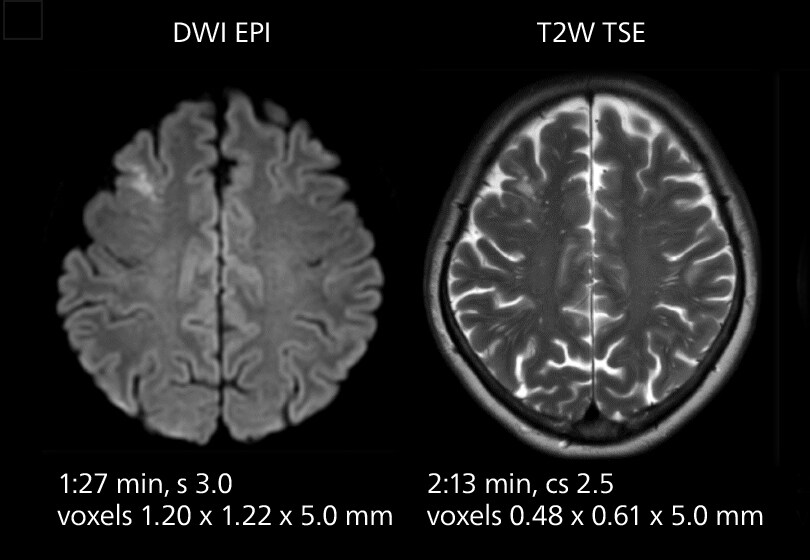

These images of an old cerebral infarction demonstrate the speed and image quality after upgrading to Elition X.

Crisp images are obtained with high resolution and short scan times using Elition X. A cyst can be seen.